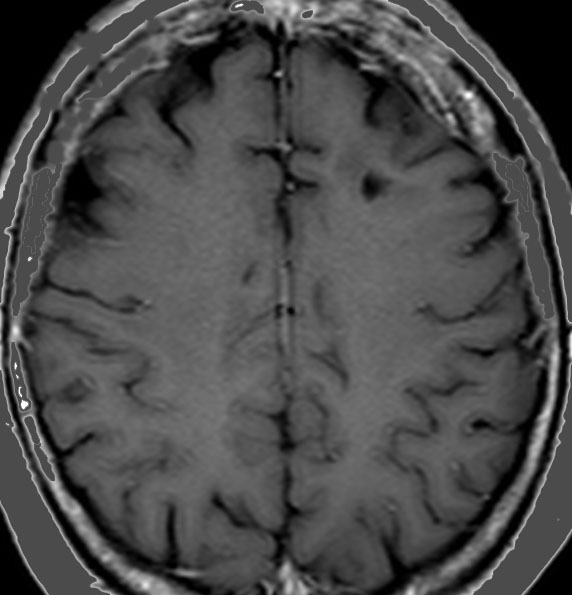

典型的な転移性脳腫瘍(単発)のMRI

腺癌の左前頭葉転移です。左のガドリニウム造影剤を使った画像では腫瘍が白く写っています。腫瘍の内部が一部壊死しているので黒っぽく見えます。右はフレア画像です。腫瘍の周囲の脳が腫れて脳浮腫(白く滲むようなところ)を生じています。

開頭手術で摘出した半年後の画像です。腫瘍は再発していなくて,脳の腫れも引いています。転移が発見された時には,見当識障害などの左前頭葉症状が強かったし,摘出がとても簡単な場所だったので手術しました。線状皮膚切開・小開頭ですから1時間くらいの簡単な手術です。でも,26mmくらいでしたから,定位放射線治療も可能なものでした。この患者さんは幸いなことに半年で再発していませんが,開頭手術による摘出だけだと同じ場所からまた再発することもあり,それから放射線治療を加えなくてはならないこともあります。個々の判断は難しいのですが,基本的には開頭手術より定位放射線治療のほうがいいと考えて下さい。